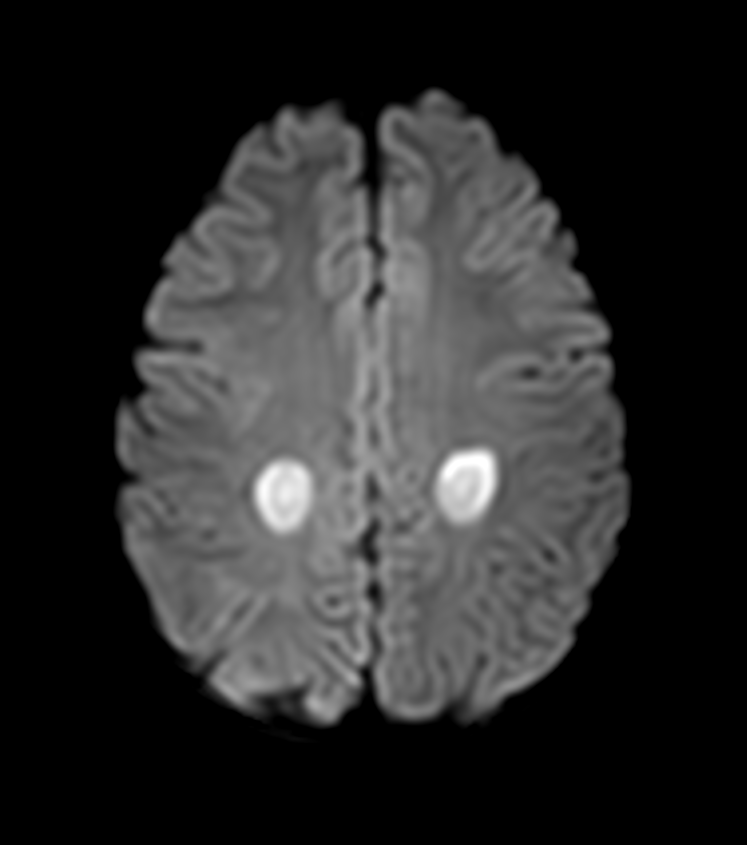

- DWI/ADC:

- Restricted diffusion (high DWI, low ADC) in acute toxicity

- Normalization or facilitated diffusion in chronic phase

- May show "reversal sign" with resolution

- T2/FLAIR:

- Symmetric hyperintense periventricular white matter lesions

- Centrum semiovale involvement common